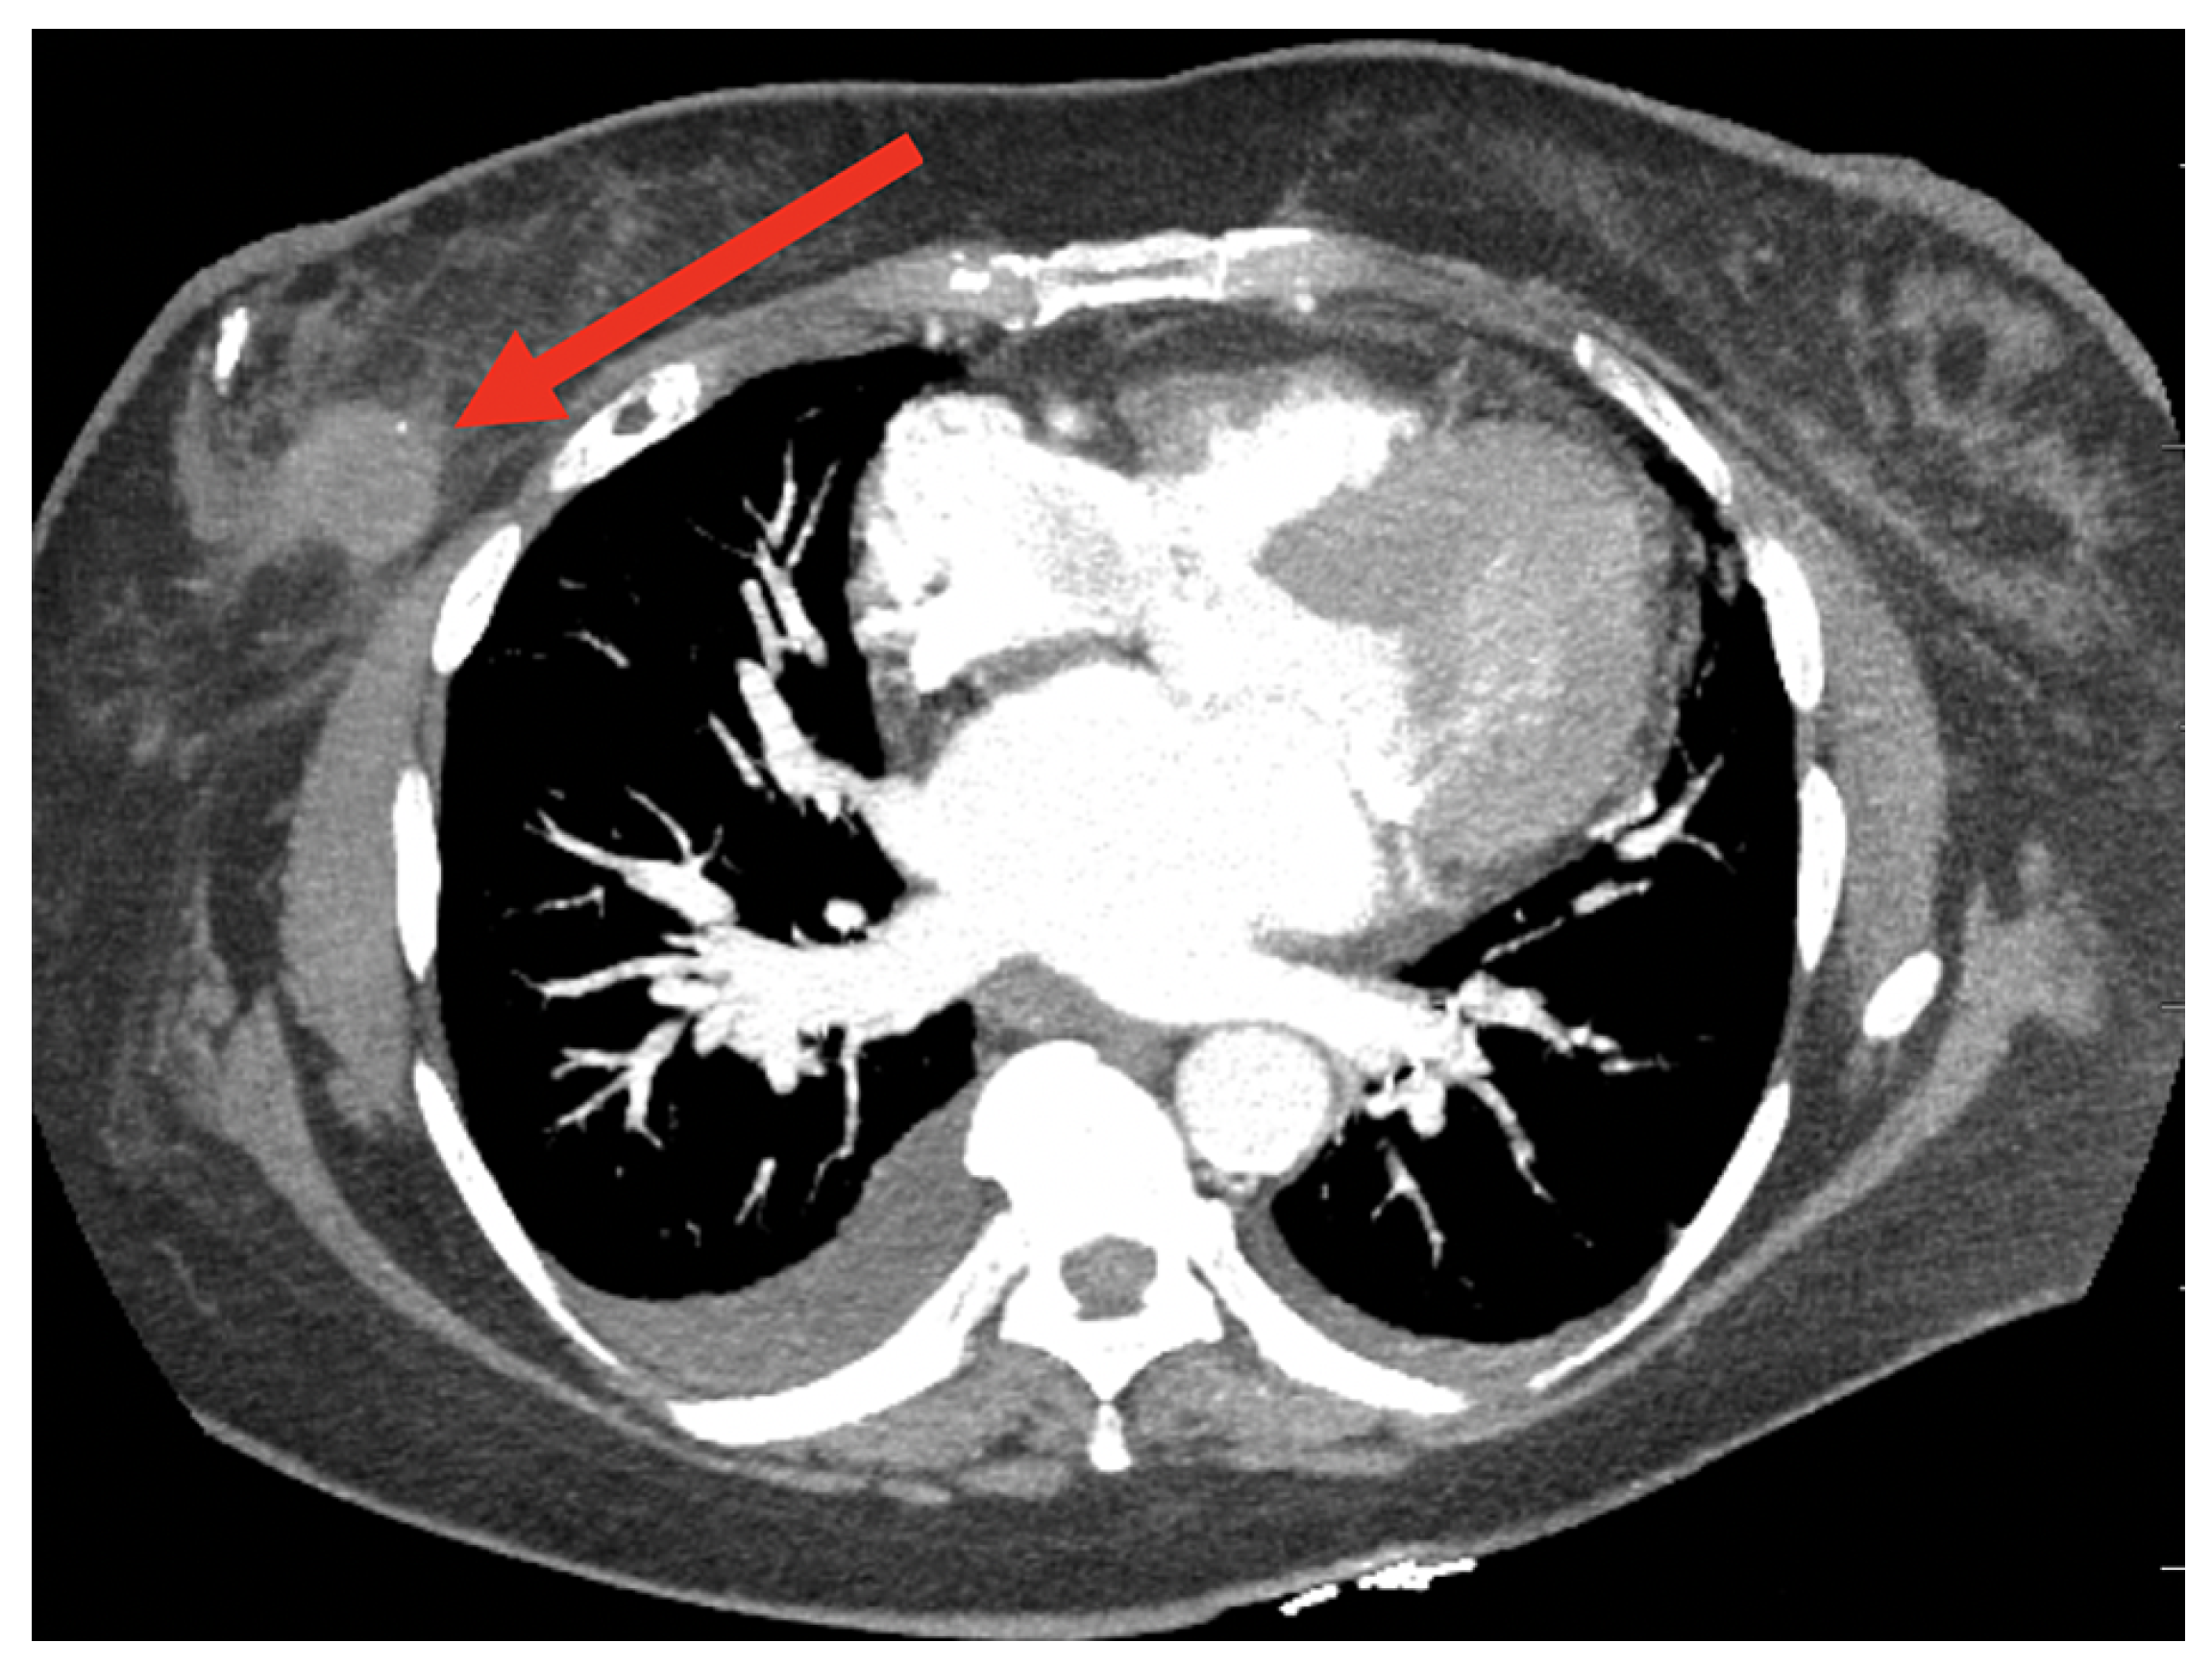

8.4. Breast Cancer Detection Using Computed Tomography (CT) Scan Images

8.4.1. Model Performance on CT Image: Pros, Cons, and Future Directions